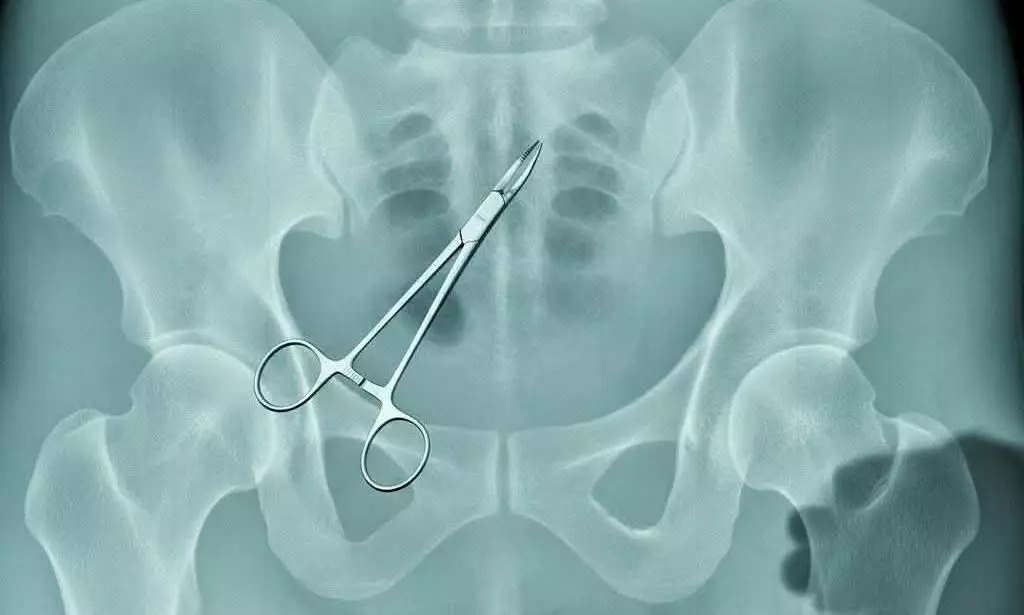

കോഴിക്കോട്: വണ്ടാനം മെഡിക്കല് കോളജില് വയറ്റില് കത്രിക കുടുങ്ങിയ സംഭവത്തില് സംസ്ഥാന സര്ക്കാരിനെതിരേ വിമര്ശനവുമായി കെപിസിസി വര്ക്കിങ് പ്രസിഡന്റ് ഷാഫി പറമ്പില് എംപി. ഉഷ എന്ന സഹോദരിയുടെ അല്ല, പിണറായി സര്ക്കാരിന്റെ എക്സറേയാണിതെന്ന് ഫേസ്ബുക്കിലെഴുതിയ കുറിപ്പില് ഷാഫി പറഞ്ഞു.